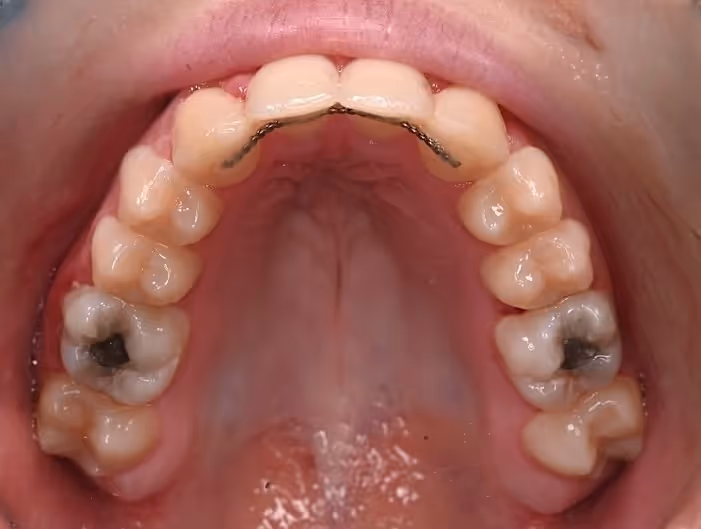

Fixed retainers – thin, discreet wires bonded to the back of the front teeth for continuous support.